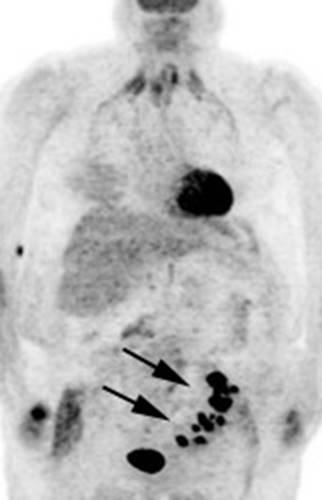

Figure 16 - Focal colonic uptake

associated with colon cancer: This patient had focal tracer uptake in the region of the cecum. CT

demonstrated a soft tissue mass which was found to be a primary colon cancer on

colonoscopy. Focal areas of colonic tracer uptake should be further evaluated.